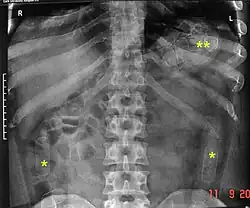

Routine detection of the smuggled packets is extremely difficult, and many cases come to light because a packet has ruptured or because of intestinal obstruction. Unruptured packets may sometimes be detected by rectal or vaginal examination, but the only reliable way is by X-ray of the abdomen. Hashish appears denser than stool, cocaine is approximately the same density as stool, while heroin looks like air.[11][12]

An increasingly popular type of swallowing involves having the drug in the form of liquid-filled balloons or condoms/packages. These are impossible to detect unless the airport has high-sensitivity X-Ray equipment, as a liquid mixture of water and the drug will most likely not be detected using a standard X-Ray machine. Most of the major airports in Europe, Canada, and the US have the more sensitive machines.